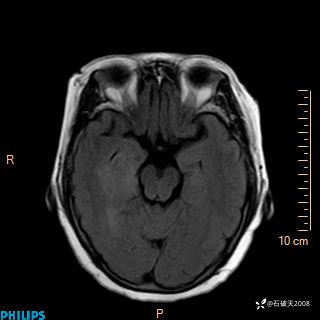

颅内占位,影像征象不是很丰富,有病理

hyy838 推荐女 62岁 主 诉:头晕12小时,加重1小时。

现病史:患者于12小时前无明显诱因出现头晕,呈持续性,无天旋地转及行走不稳,伴恶心、呕吐,呕吐共5次,呕吐物为胃内容物(具体性质不详),无胸闷、胸痛、心慌,无腹痛、腹泻,无咳嗽、咳痰,无发热、意识不清、肢体抽搐及大小便失禁等,1小时前患者上述症状加重,未诊疗,为求进一步治疗急自行来我院,门诊以“头晕待查”为诊断收入我科,发病来,神志清,精神差,饮食、睡眠差,大小便正常,体重未见明显下降。

DWI

ADC